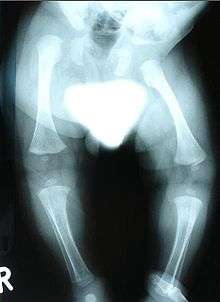

- X-ray, to look for bone abnormalities

Congenital distal spinal muscular atrophy (congenital dSMA) is a hereditary genetic condition characterized by muscle wasting (atrophy), particularly of distal muscles in legs and hands, and by early-onset contractures (permanent shortening of a muscle or joint) of the hip, knee, and ankle. Affected individuals often have shorter lower limbs relative to the trunk and upper limbs. The condition is a result of a loss of anterior horn cells localized to lumbar and cervical regions of the spinal cord early in infancy, which in turn is caused by a mutation of the TRPV4 gene. The disorder is inherited in an autosomal dominant manner.[1] Arm muscle and function, as well as cardiac and respiratory functions are typically well preserved.[2]